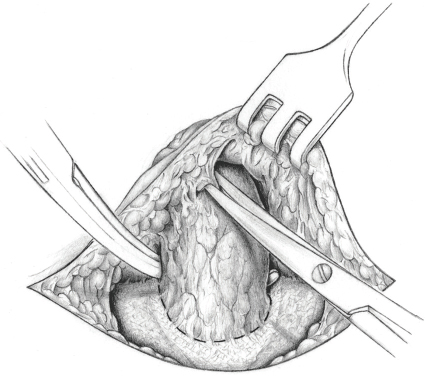

If a sliding hernia is suspected based on the consistency of the hernial sac, the sac is opened between clamps on the anterior wall (

Fig. 3.6). It must be ensured that only the anterior peritoneal layer is divided; so, no part of the bowel is injured. Opening the sac of small medial sliding hernias can be omitted when the bladder forms part of the wall. In these cases, a superficial purse string suture suffices to bury the sac.

In the case of larger sliding hernias, the sac must be opened at the lateral and medial border of the sliding component as far as the deep inguinal ring (

Fig. 3.7). This enables the sac contents to be reduced. Reperitonealization should not be attempted because of the risk of injury.

Fig. 3.6 Sliding hernia. It is repaired by creating a new peritoneal ring, incising the free peritoneum.